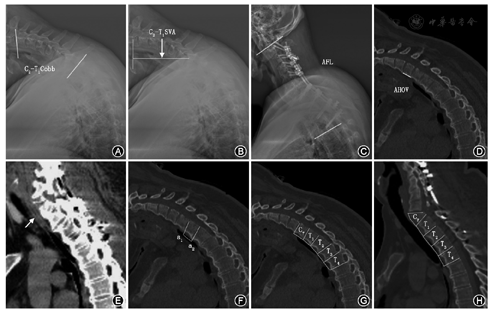

于术前、术后颈椎侧位X线片上测量脊柱矢状面参数,在患者外观照片上测量颏眉角(CBVA)[12]。食管在颈胸段沿椎体前缘下行,故可在CT矢状面重建上测量颈胸段部分食管长度(图1)。颈胸段后凸Cobb角:上端固定椎下终板与T1下终板的夹角(后凸为正,前凸为负)。颈胸段矢状面平衡(C2-T1SVA):过C2中心的铅垂线与T1椎体后上缘之间的距离。固定节段角度(AFL):固定节段上端椎下终板与下端椎下终板之间Cobb角(后凸为正,前凸为负)。颏眉角(CBVA):即在伸髋、伸膝直立位,侧位外观上下颌与眉弓连线与铅垂线之间夹角。截骨椎前缘高度(AHOV):即C7椎体前缘上下终板之间距离。部分食管长度[13]:平行于椎体上终板的线与平行于食管后缘的线形成的交点(a1)和平行于相邻下椎体上终板的线与平行于食管后缘的线形成的交点(a2)之间的连线即为一段食管长度。部分食管长度为C6下终板至下端固定椎下终板之间每一段食管长度相加。

8例患者术前颈胸段后凸Cobb角平均为20.3°±10.4°(5°~37°),术后为-15.3°±8.9°(-30°~-3°),矫正值为35.9°±7.3°。固定节段角度(AFL)术前、术后分别平均为34.6°±12.2°(5°~51°)、2.6°±12.3°(-21°~22°)。C2-T1SVA术前为(95±19)mm(52~120 mm),术后改善至(51±16)mm(15.3~72.2 mm),平均矫正率为47.7%。术前颏眉角(CBVA)平均为47.0°±10.9°(33°~65°),术后改善至8.9°±7.7°(-8°~21°),矫正值为38.1°±11.5°,平均矫正率77.4%(表1,图1)。

术前、术后AHOV分别为(16.7±1.3)mm(14.1~17.7 mm)、(11.1±1.5)mm(9.0~14.0 mm);食管起始处(C6下终板)至下固定椎下终板间的食管长度分别为(99.5±8.7)mm(89.8~120.5 mm)、(115.4±9.6)mm(101.6~137.3 mm)(表2)。